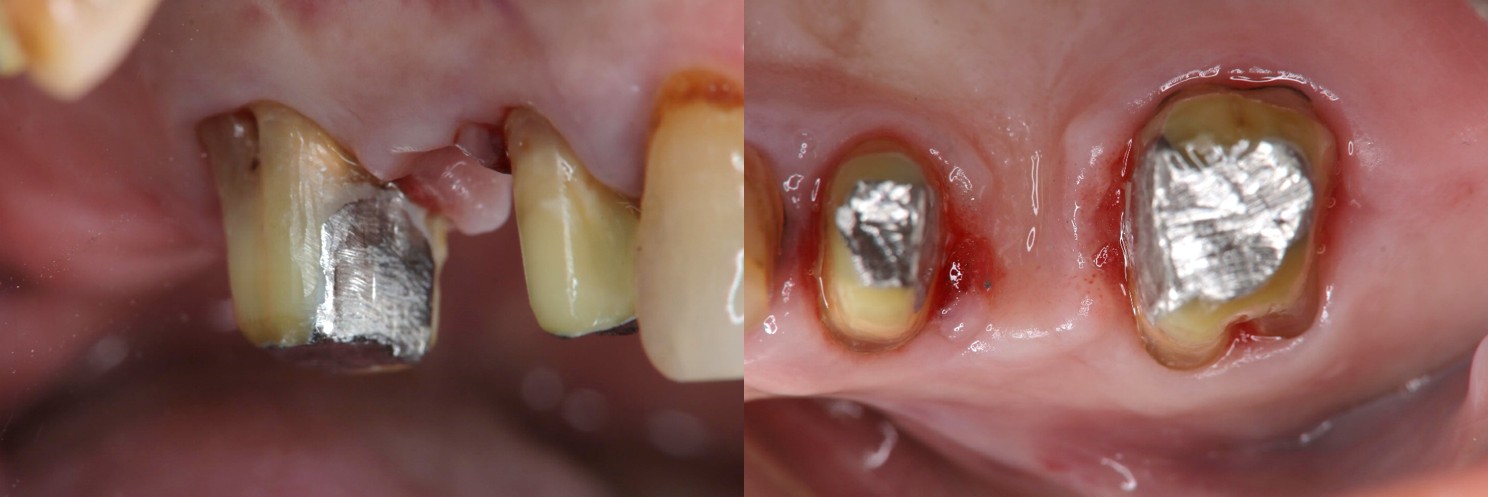

膺復前評估牙齦、牙齒狀態